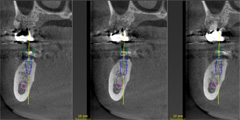

Straumann CARES ガイデッドサージェリー

コンピューターによるシミュレーションソフトウェア“coDiagnostiX”、ガイド製作用装置“gonyX”、そして専用のサージカルガイドにより構成された一貫したシステムにより、手術精度と安全性を劇的に向上させる事を可能にする包括型ソリューション。

サージカルガイド

従来のインプラント埋入手術方法は術者の経験、スキル、感によるのもであった。しかし、Straumann CARES ガイデッドサージェリーで作製されたサージカルガイドを手術時に装着する事により、システマティックなインプラントの埋入深度と埋入角度を実現する事が可能。これにより、術後出血や術後神経麻痺等の合併症を回避でき飛躍的に手術安全性が向上できる。